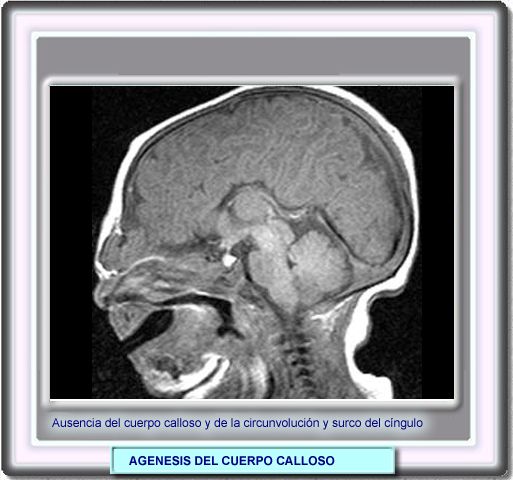

La agenesis puede sospecharse en las ecografías de rutina y se pone de manifiesto mediante la RM como en este caso